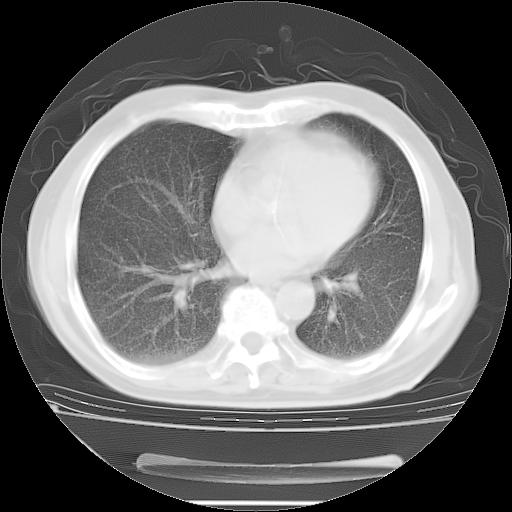

今天复查肺部CT,发现双肺广泛磨玻璃样改变。所以我把3月19日和5月9日相隔50天的肺部CT上传。请大家会诊。

2009年3月19日肺部CT片。

2009年3月19日肺部CT

大致读了系列胸部CT:纵隔窗无明显异常,肺窗:从4、27至今:主要是双肺中下野外带可见毛玻璃样改变,目前处于急性肺泡炎阶段,至于原因考虑1、结替组织或胶原血管性疾病所致?2、恶性疾病如恶组在肺部所致的表现或细支气管肺泡癌?3、药物或其它原因如肺蛋白沉着症所致肺泡炎目前不太可能?总之,明天就去请我院的呼吸科、感染科、血液科和临免专家会诊哈。